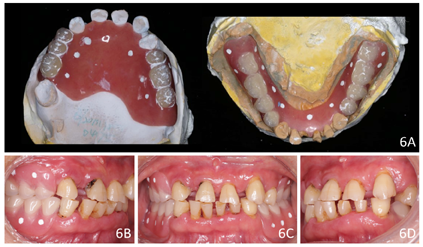

治疗过程:(1)术前准备:①藻酸盐取初印模,制作个性化托盘(图4);②用个性化托盘取硅橡胶终印模,灌制终模型;③制作光固化树脂

托及蜡堤(图5),面部比例二等分法确定垂直距离,肌肉疲劳法及吞咽咬合法确定水平关系,面弓转移患者颌位关系,上

架;④排牙,制作放射导板(图6A);⑤试戴放射导板(图6B~D),拍摄两次CBCT(患者佩戴放射导板拍摄CBCT以及放射导板单独拍摄CBCT)。(2)方案设计:①将两次CBCT获取的DICOM数据导入种植设计软件重叠(图7),以修复为导向指导上下颌种植体位置摆放(图8、图9);②生成并打印手术导板(图10)。(3)利用手术导板和导板锁,翻制模型,制作临时修复体(图11)。(4)一期手术过程:铺巾消毒,局麻后拔除上下颌余留牙,搔刮拔牙窝内炎性肉芽组织,于34-36、44-46区牙槽嵴顶近远中向切开牙龈,翻瓣。就位并固定手术导板,于11、13、16、22、25、26、32、34、36、42、44、46定点,按术前设计方案植入NobelParallelTM ConicalConnection种植体。除26区种植体外,其余种植体初期稳定性均达到35N.cm以上,就位复合基台,戴入保护帽,修整牙龈黏膜,缝合牙龈(图12A~F)。术后拍摄全景片(图13)。次日复诊,取下保护帽,戴入预制的临时修复体,调合(图12G)。